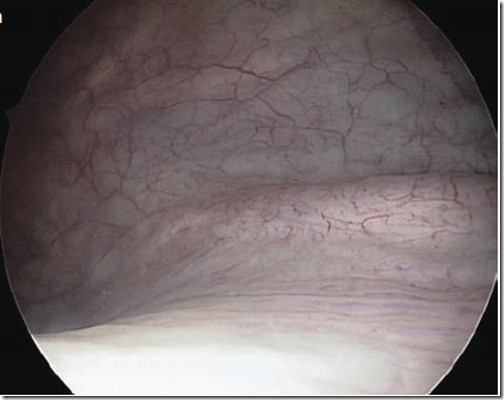

Imagen: Se aprecia el interior de la vejiga a través de un cistoscopio. Atlas of Urogynecological Endoscopy. Peter L. Dwyer, 2007

La cistoscopía  es un procedimiento mediante el cual se visualiza el  interior de la uretra y la vejiga  a través de un instrumento óptico llamado cistoscopio. Cuando usted tiene un problema en la vejiga se puede emplear un cistoscopio para examinar el interior de la vejiga y uretra (tubo que conduce la orina desde la vejiga hasta su salida fuera del cuerpo).